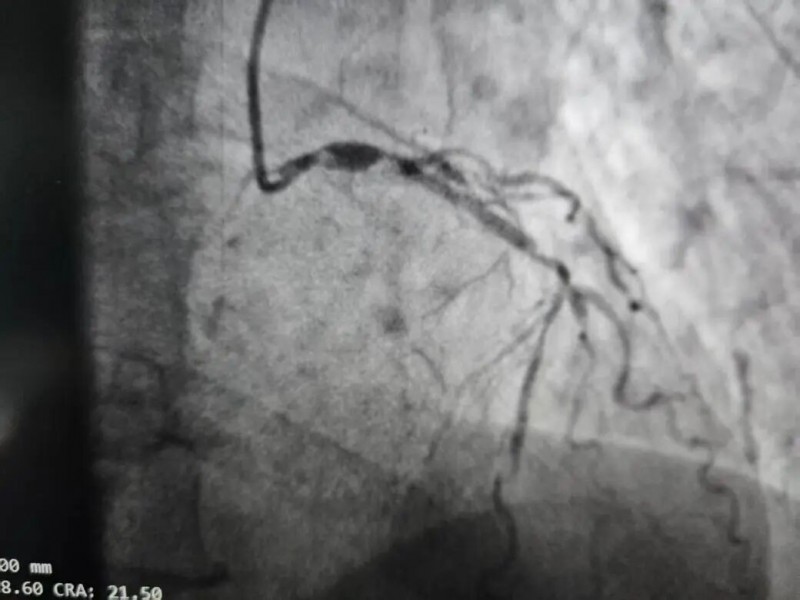

李先生,70岁,徐州沛县某镇人。胸闷心悸折磨了他整整一年,近两个月更是急剧加重。在两家三甲医院辗转就医后,4月7日的冠脉造影结果让在场的医生倒吸一口凉气——

右冠状动脉近中段弥漫长病变伴重度钙化,最重处狭窄90%;左主干到左前降支开口狭窄95%伴重度钙化;左回旋支近段闭塞……

冠脉三支+左主干重度狭窄!

通俗点说,这位老人心脏上最重要的三条血管和总阀门,几乎全部堵死。他的心脏就像一枚随时可能引爆的“炸弹”,每一次情绪波动、每一次轻微活动,都可能诱发心源性猝死。